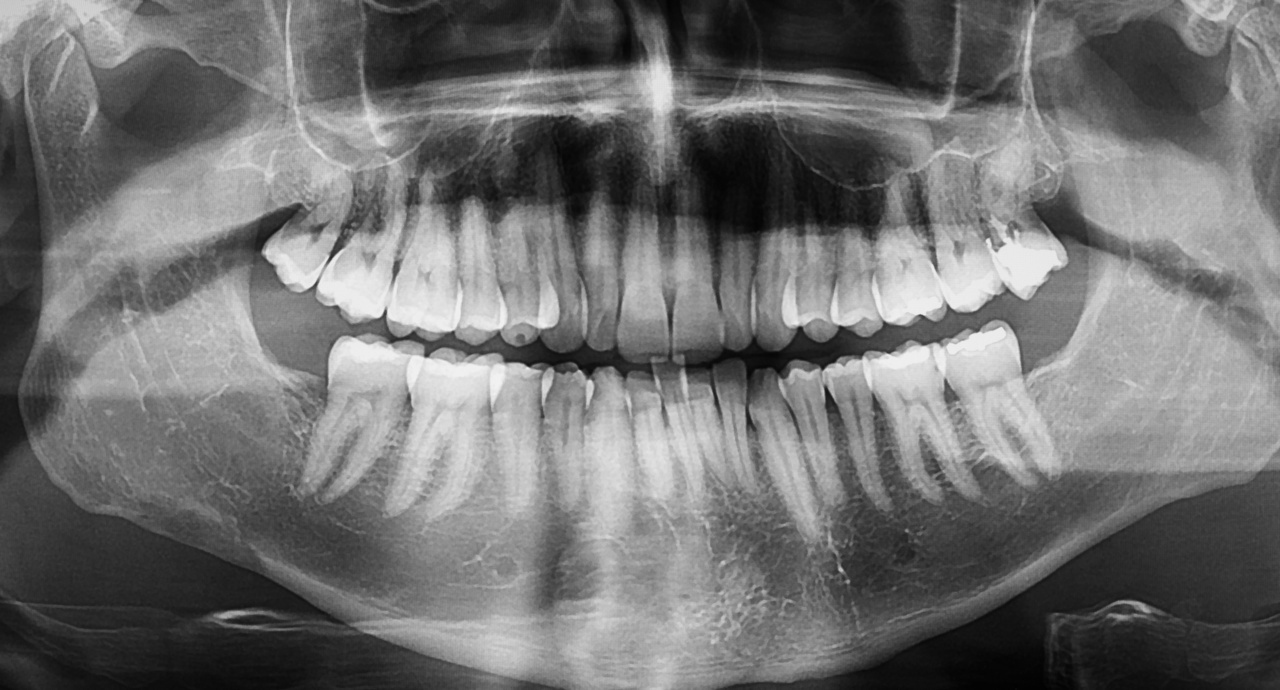

矯正検査

お口の写真やレントゲン、歯型などを取らせていただきます。治療計画の立案・検討を行います。